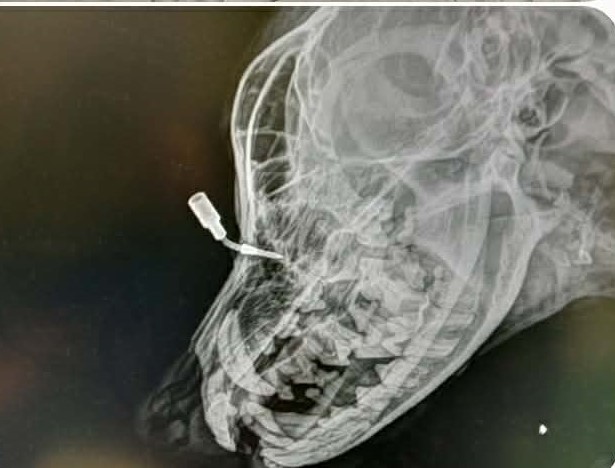

Névtelen Közzétéve: 2026. március 6. péntek | Kategória: A HOMLOKÁBAN VOLT EZ A LÖVEDÉK!!!Teljes felbontás (615 × 468) ← Előző